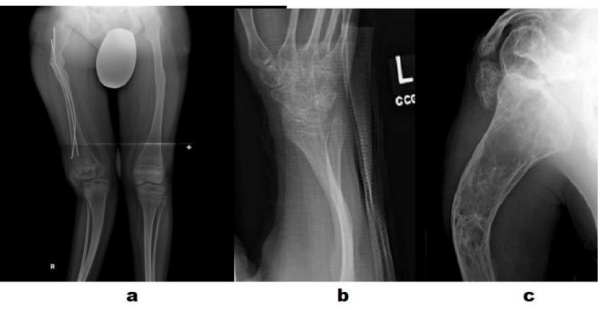

❖ Xương dài: Hay gặp nhất là gãy xương do chấn thương nhẹ, thường gặp nhất là xương chi dưới trong đó xương đùi nhiều hơn xương chày. Có thể gãy xương không do chấn thương. Không có kiểu hình gãy nào là đặc hiệu cho OI. Thường xương gãy liền tốt ít khi tạo khớp giả. Ổ can xương thường mỏng. Gãy đi gãy lại dẫn đến biến dạng trục chi, cứng khớp, hạn chế hoặc mất vận động. Trẻ không lớn được do các vi chấn thương ở sụn tiếp. Tuổi thường hay bị gãy xương nhất là sau khi dậy thì và có thể kéo dài đến khi mãn kinh ở các trẻ gái. Biến dạng cong xương dài là do lặp đi lặp lại các đường gãy ngang và sự co kéo các cơ qua ổ gãy thân xương. Thường thì xương đùi sẽ cong ra phía trước ngoài, xương chày cong phía trước trong, xương cánh tay cong ra trước ngoài, xương cẳng tay hạn chế sấp và gập góc đầu gần. Khớp khuỷu hạn chế động tác gấp.

❖ Xquang: phát hiện gãy xương, biến dạng trục chi, các ổ gãy xương cũ. Các đặc điểm khác có thể phát hiện trên Xquang: vỏ xương mỏng, giảm khoáng hóa, xương sọ giống người đội mũ bảo hiểm… Trong trường hợp điển hình thì kết hợp Xquang và tiền sử gãy xương nhiều lần có thể chẩn đoán OI.

- Dụng cụ: Đinh không lồng vào nhau (Rush, Williams), đinh lồng vào nhau giúp đinh tự kéo dài khi trẻ lớn (Sheffied rod, Bailey- Dubow rod, Fassier-Duval rod).

Kĩ thuật cắt xương chỉnh trục và đặt đinh nội tủy

Các dụng cụ thường được dùng : (A) Đinh Bailey-Dubow; (B) Bailey-Dubow có chốt ngang đầu dưới (C) Đinh Fassier-Duval (D) dual Rush rods: áp dụng với trường hợp trẻ có xương dài ống tủy rộng, hiện nay chưa thấy biến chứng kiểu chồng nhau bên ngoài của đinh Rush